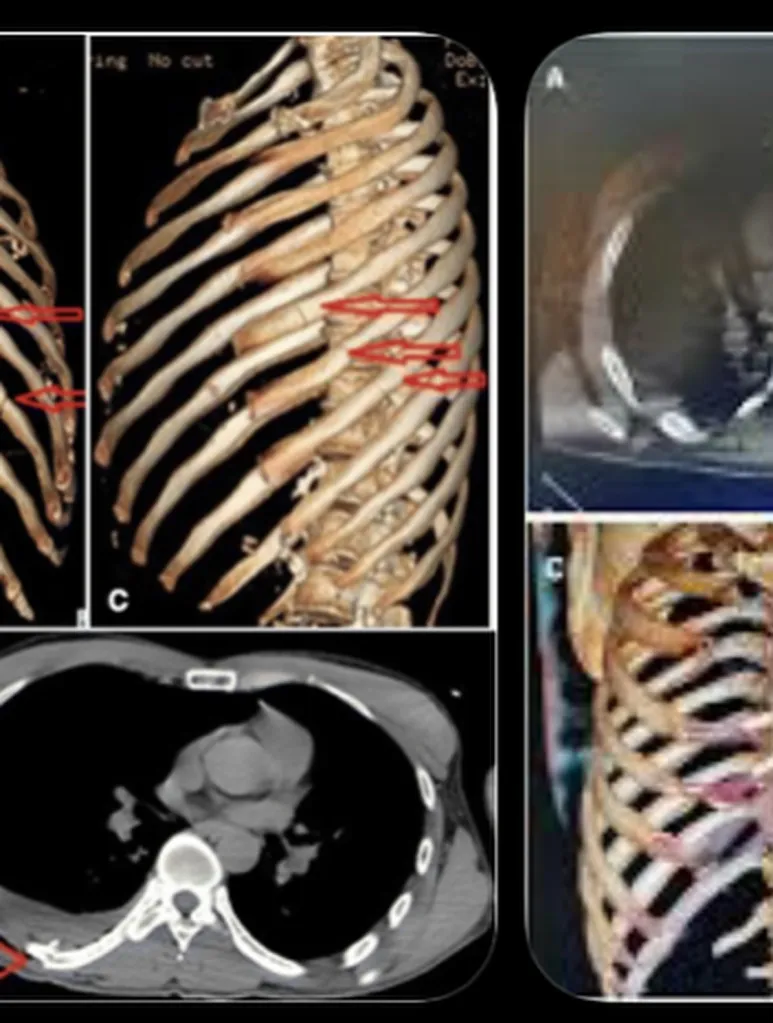

Помимо 11 сломанных ребер, Чеймберс сообщил, что 42-летний Кори также получил повреждение легкого, сотрясение мозга и внутренние кровотечения.

«Довольно плохо, но я в порядке», — написал он рядом с фотографиями из больницы. «Защитные дуги очень хороши. Три ночи в больнице. 11 переломов в грудной клетке».